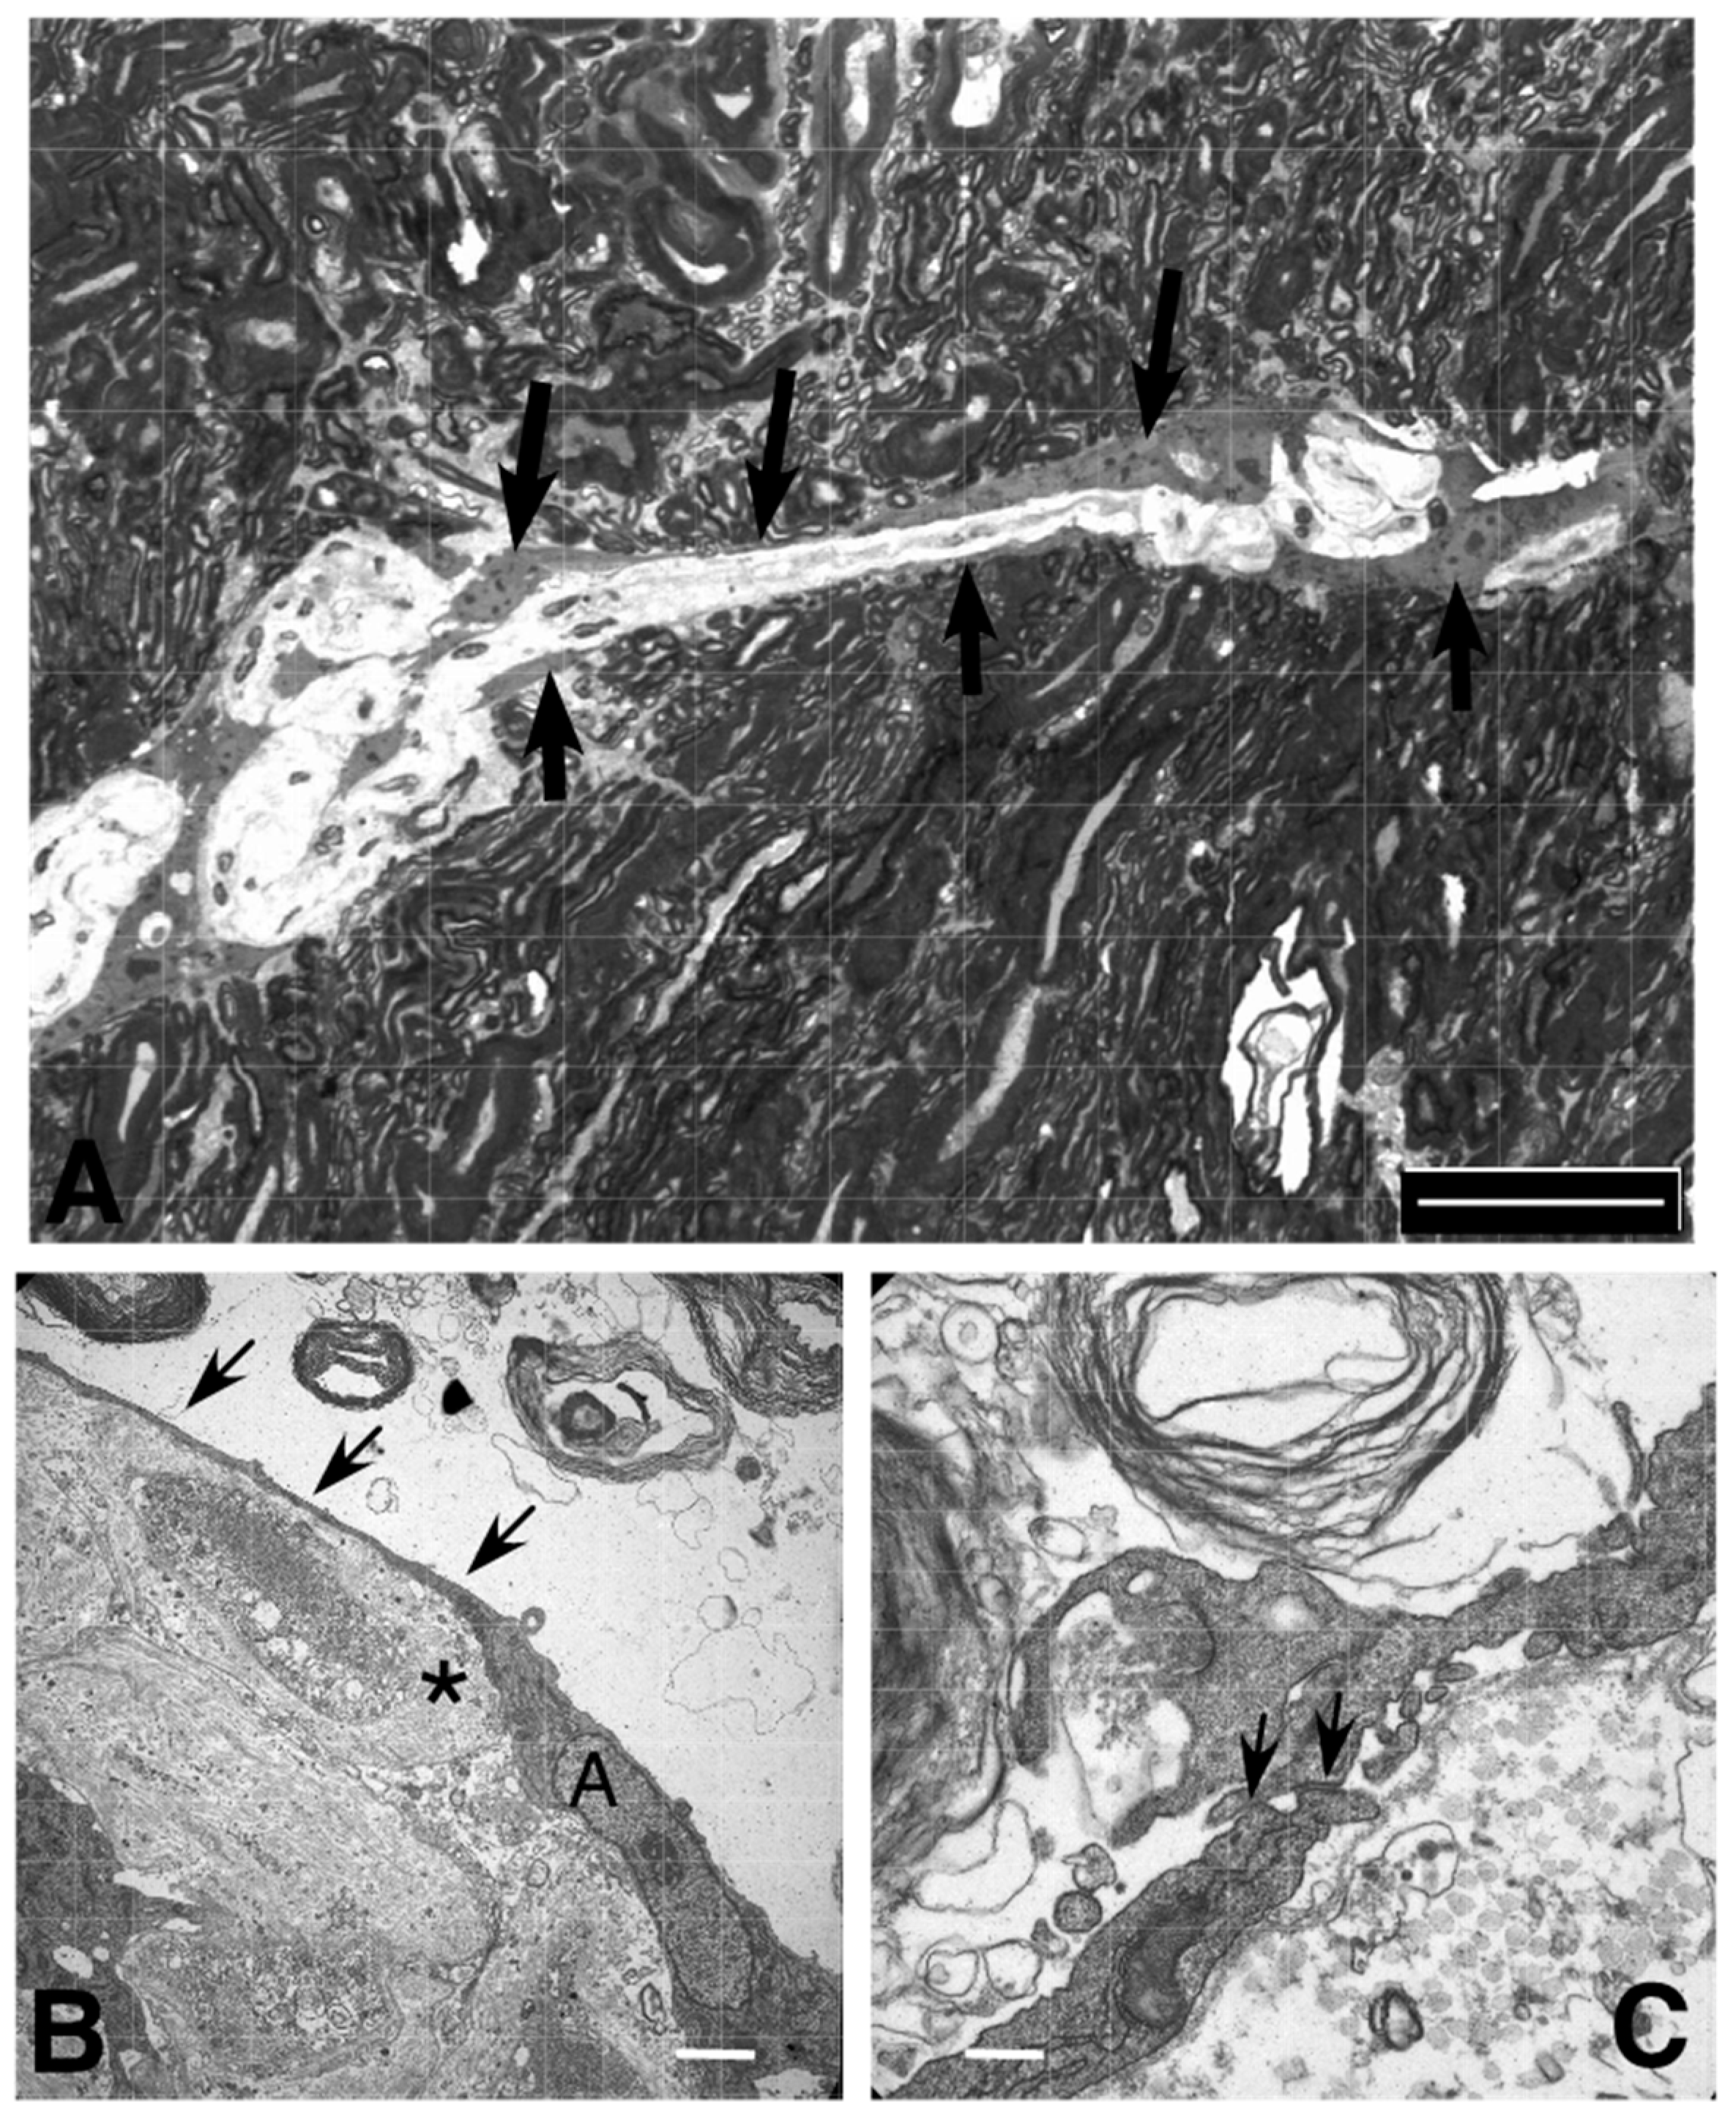

2.5.3. Organotypic Porcine Spinal Slice Migration (OPoSSM) Assay

3. Discussion